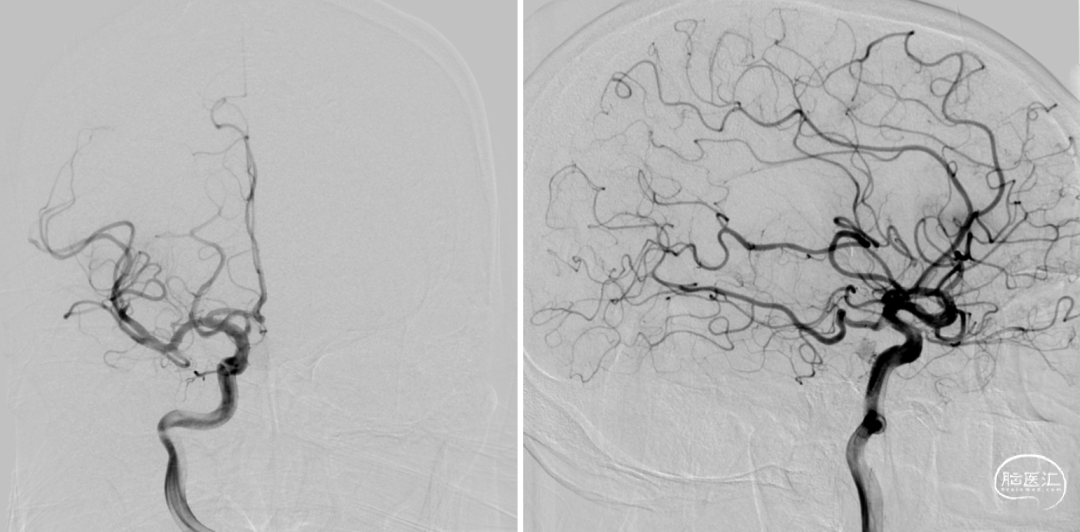

缓慢回收支架并负压抽吸,可见支架显影性良好,同时JRecanTM远端闭合设计有效防止血栓逃逸

最终造影结果mTICI 2b

术后复查血管通畅,少许梗塞

术后第2天NIHSS评分2分